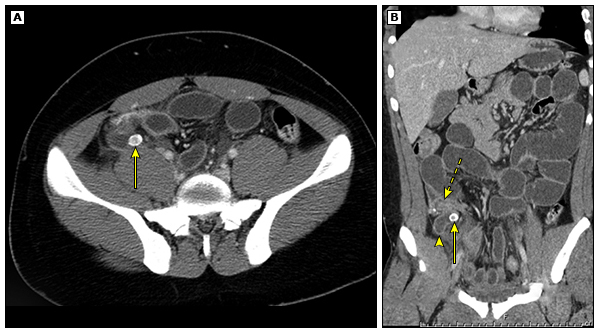

10

Q

A

-fat stranding

-inflammation extending up distal cecum

-fat in that area